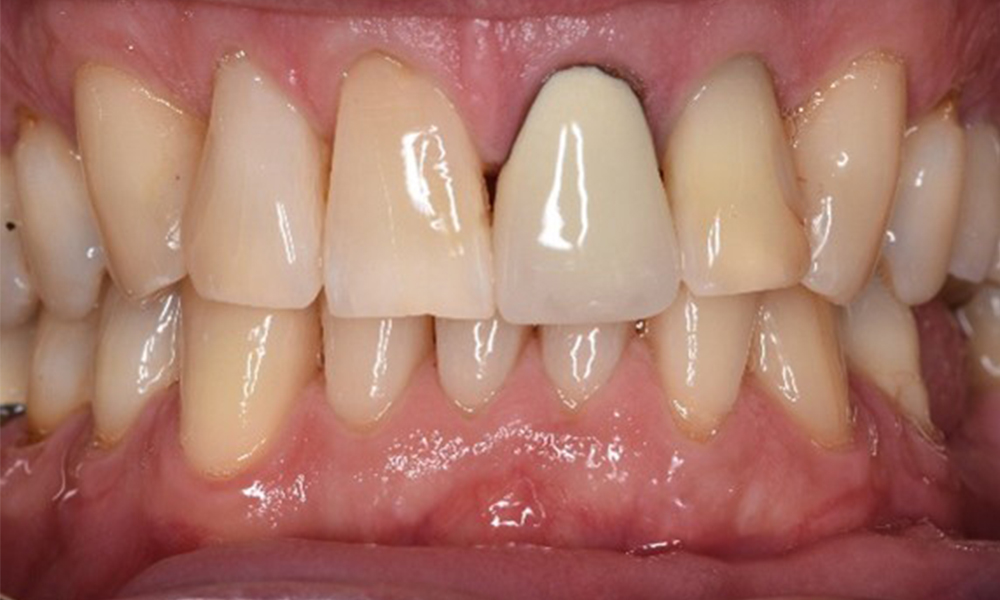

A 71-year old patient presents with having previously undergone a kidney transplant and with a history of hypertonia (high blood pressure). Due to his medical history, long-term medication with cyclosporine is required to suppress the immune system, as well as amlodipine to lower blood pressure. The patient also reports sensitive and bleeding gums. From an oral health perspective, the patient has undergone dental restoration and has eight missing teeth, pronounced gingival growth, and grade B, stage II periodontitis with active pockets and initial root caries on tooth 22. The caries risk assessment determines a moderate risk of caries (API 60). The following treatment recommendations can be determined for the prophylaxis session. more